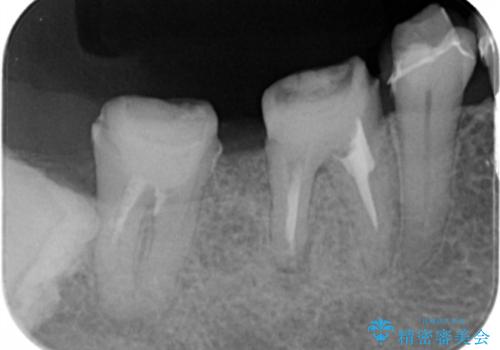

1年間他の治療を行いながら待ったのち、骨の状態確認を行う確定外科の際にしっかりと骨の再生が認められました。